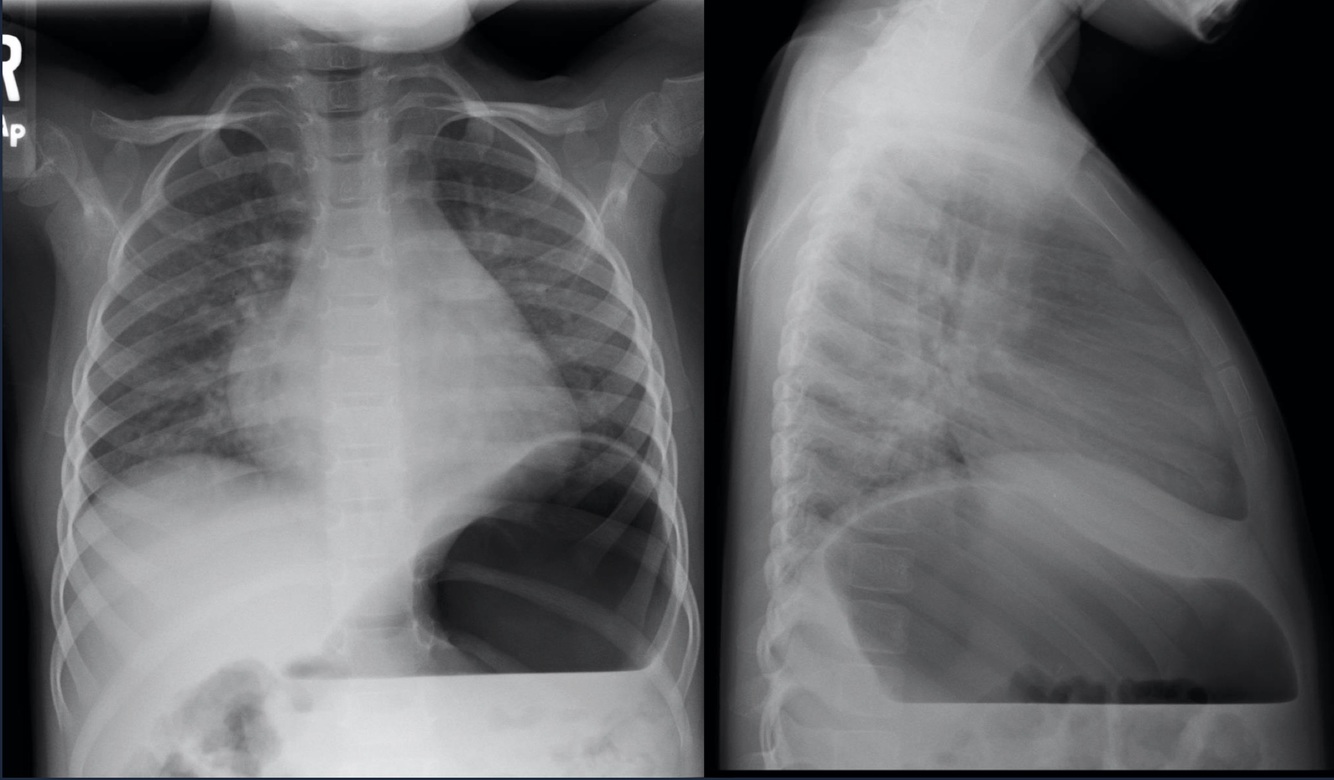

Lung Anatomy

Pulmonary Fissures

Lateral View

Can see b/l oblique fissures and horizontal fissure on the right.